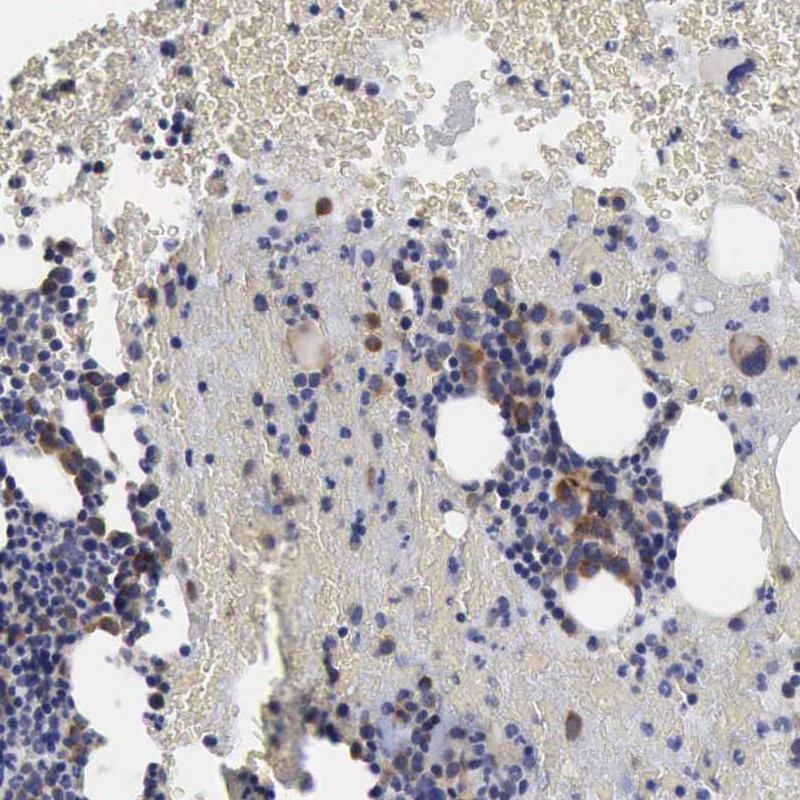

Immunohistochemical staining of human bone marrow shows distinct cytoplasmic positivity in subsets of bone marrow poietic cells.